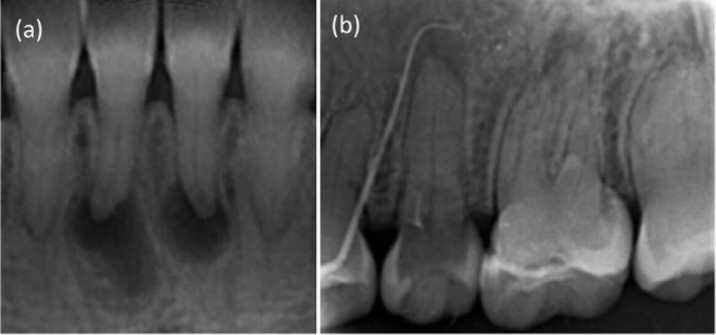

Pulp canal calcification (PCC) is common in patients with dentinogenesis imperfecta (DGI). We present endodontic management of multiple anterior and posterior teeth with PCCs in a patient with DGI type II using guided endodontics. A 26-year-old female patient was diagnosed with DGI type II. Clinical examination revealed palatal cusp fracture in tooth #13, microcracks in tooth #14, and a sinus tract in the maxillary right buccal vestibule related to tooth #13. Periapical radiographs revealed PCCs in all teeth, and periapical radiolucencies in several teeth. Due to difficult negotiation of canal orifices, guided endodontic approach was planned. Cone-beam computed tomography (CBCT) was requested and obtained. Intraoral scanning was performed, and CBCT and intraoral scanning data were superimposed. A template was designed and 3D printed. The root canal orifices were successfully negotiated and endodontic treatments were successfully accomplished. At the 1-year follow-up, the endodontically treated teeth were asymptomatic, and periapical lesions were healing.